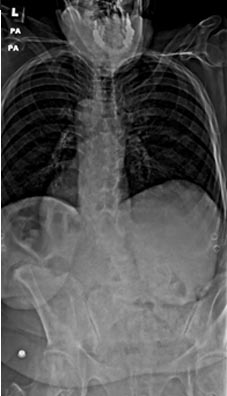

72 year old female who previously had a fusion with another surgeon who developed an infection and underwent multiple surgeries presenting with severe back pain with inability to stand upright.

46 year old woman who previously had Harrington rod spinal fusion from T4 to L3 for idiopathic adolescent scoliosis who presents with back pain and left leg weakness from severe lumbar stenosis distal to her previous fusion.

3 months postop, patient is pain free and weakness completely resolved. She is able to stand upright without pain and improved posture.